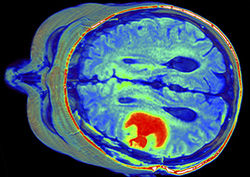

Tumores: el virus que mata o cura

La historia de un tratamiento pionero que intenta emplear un simple virus para combatir el desarrollo y los devastadores efectos de los tumores cerebrales. Twig - Biología - Las células y ADN - La defensa inmune Claves de...